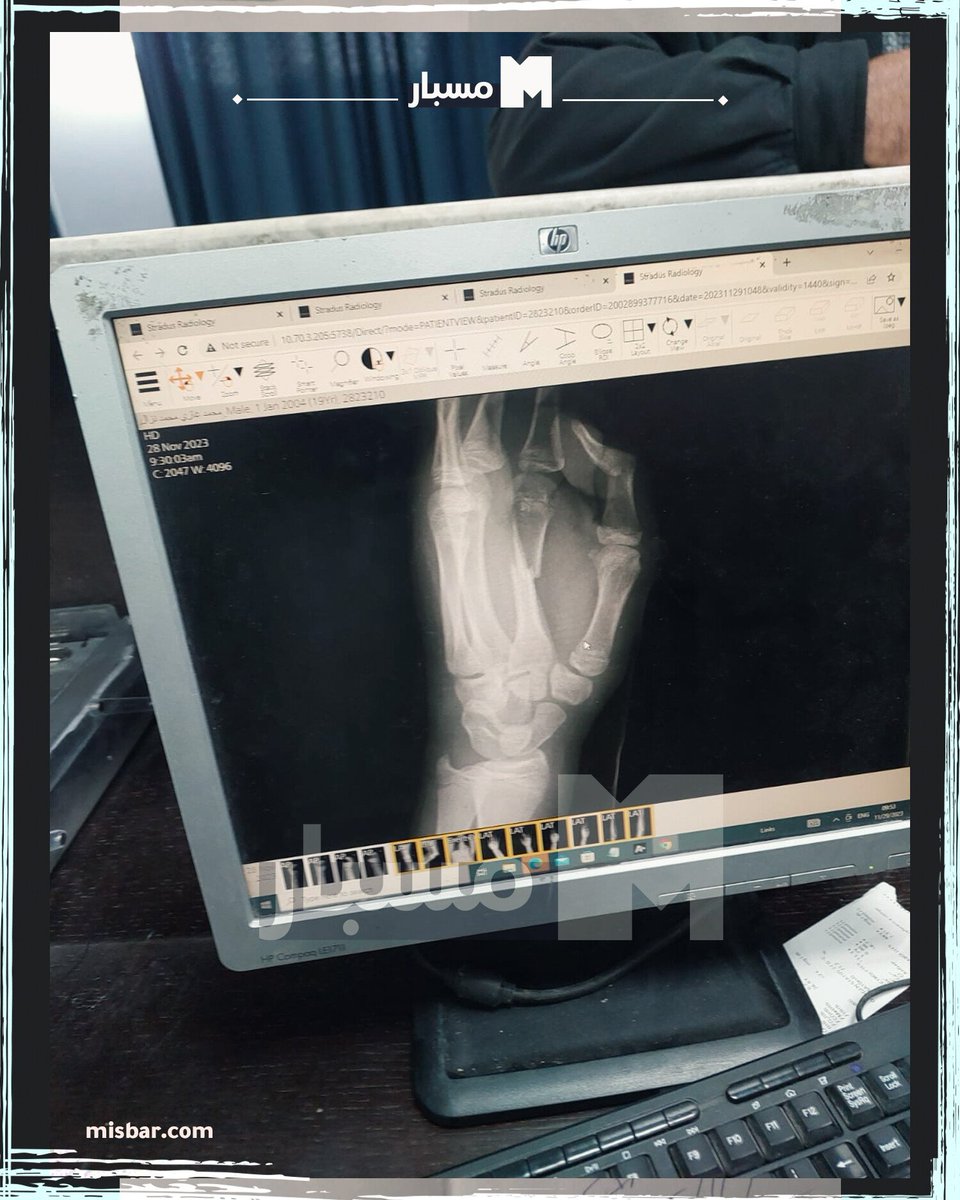

ولمزيد من التحقق، تواصل #مسبار مع عائلة محمد التي أكدت أن فحوصات أجريت له بعد خروجه للاطمئنان أكثر على صحته.

وكشفوا أن الفحوصات أكدت وجود كسور في الأصابع وتحديدًا في السبابة والإبهام في كلتا اليدين، أما باقي الأصابع فلم تصب بكسور، وهو ما يوضح سبب تحريك باقي أجزاء يده بشكل طبيعي.

وحصل #مسبار أيضًا على نسخة من صور الأشعة، أرسلتها عائلة محمد نزال وتوضح حجم الكسور في أصابعه.